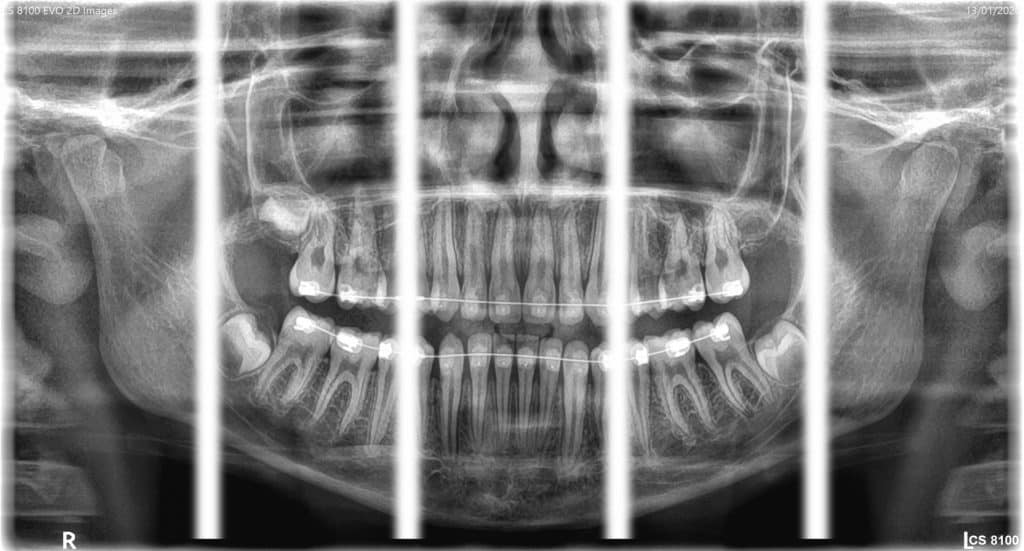

Our system CS 8100 3D Evo

- Versatile 2D/3D system

- Dose reduction technology allows a 3D scan with the dose of an OPT

- High-resolution 3D images with limited artifacts

- Clear and sharp panoramic images ideal for routine needs

Examples of image quality using the Carestream 8100 3D